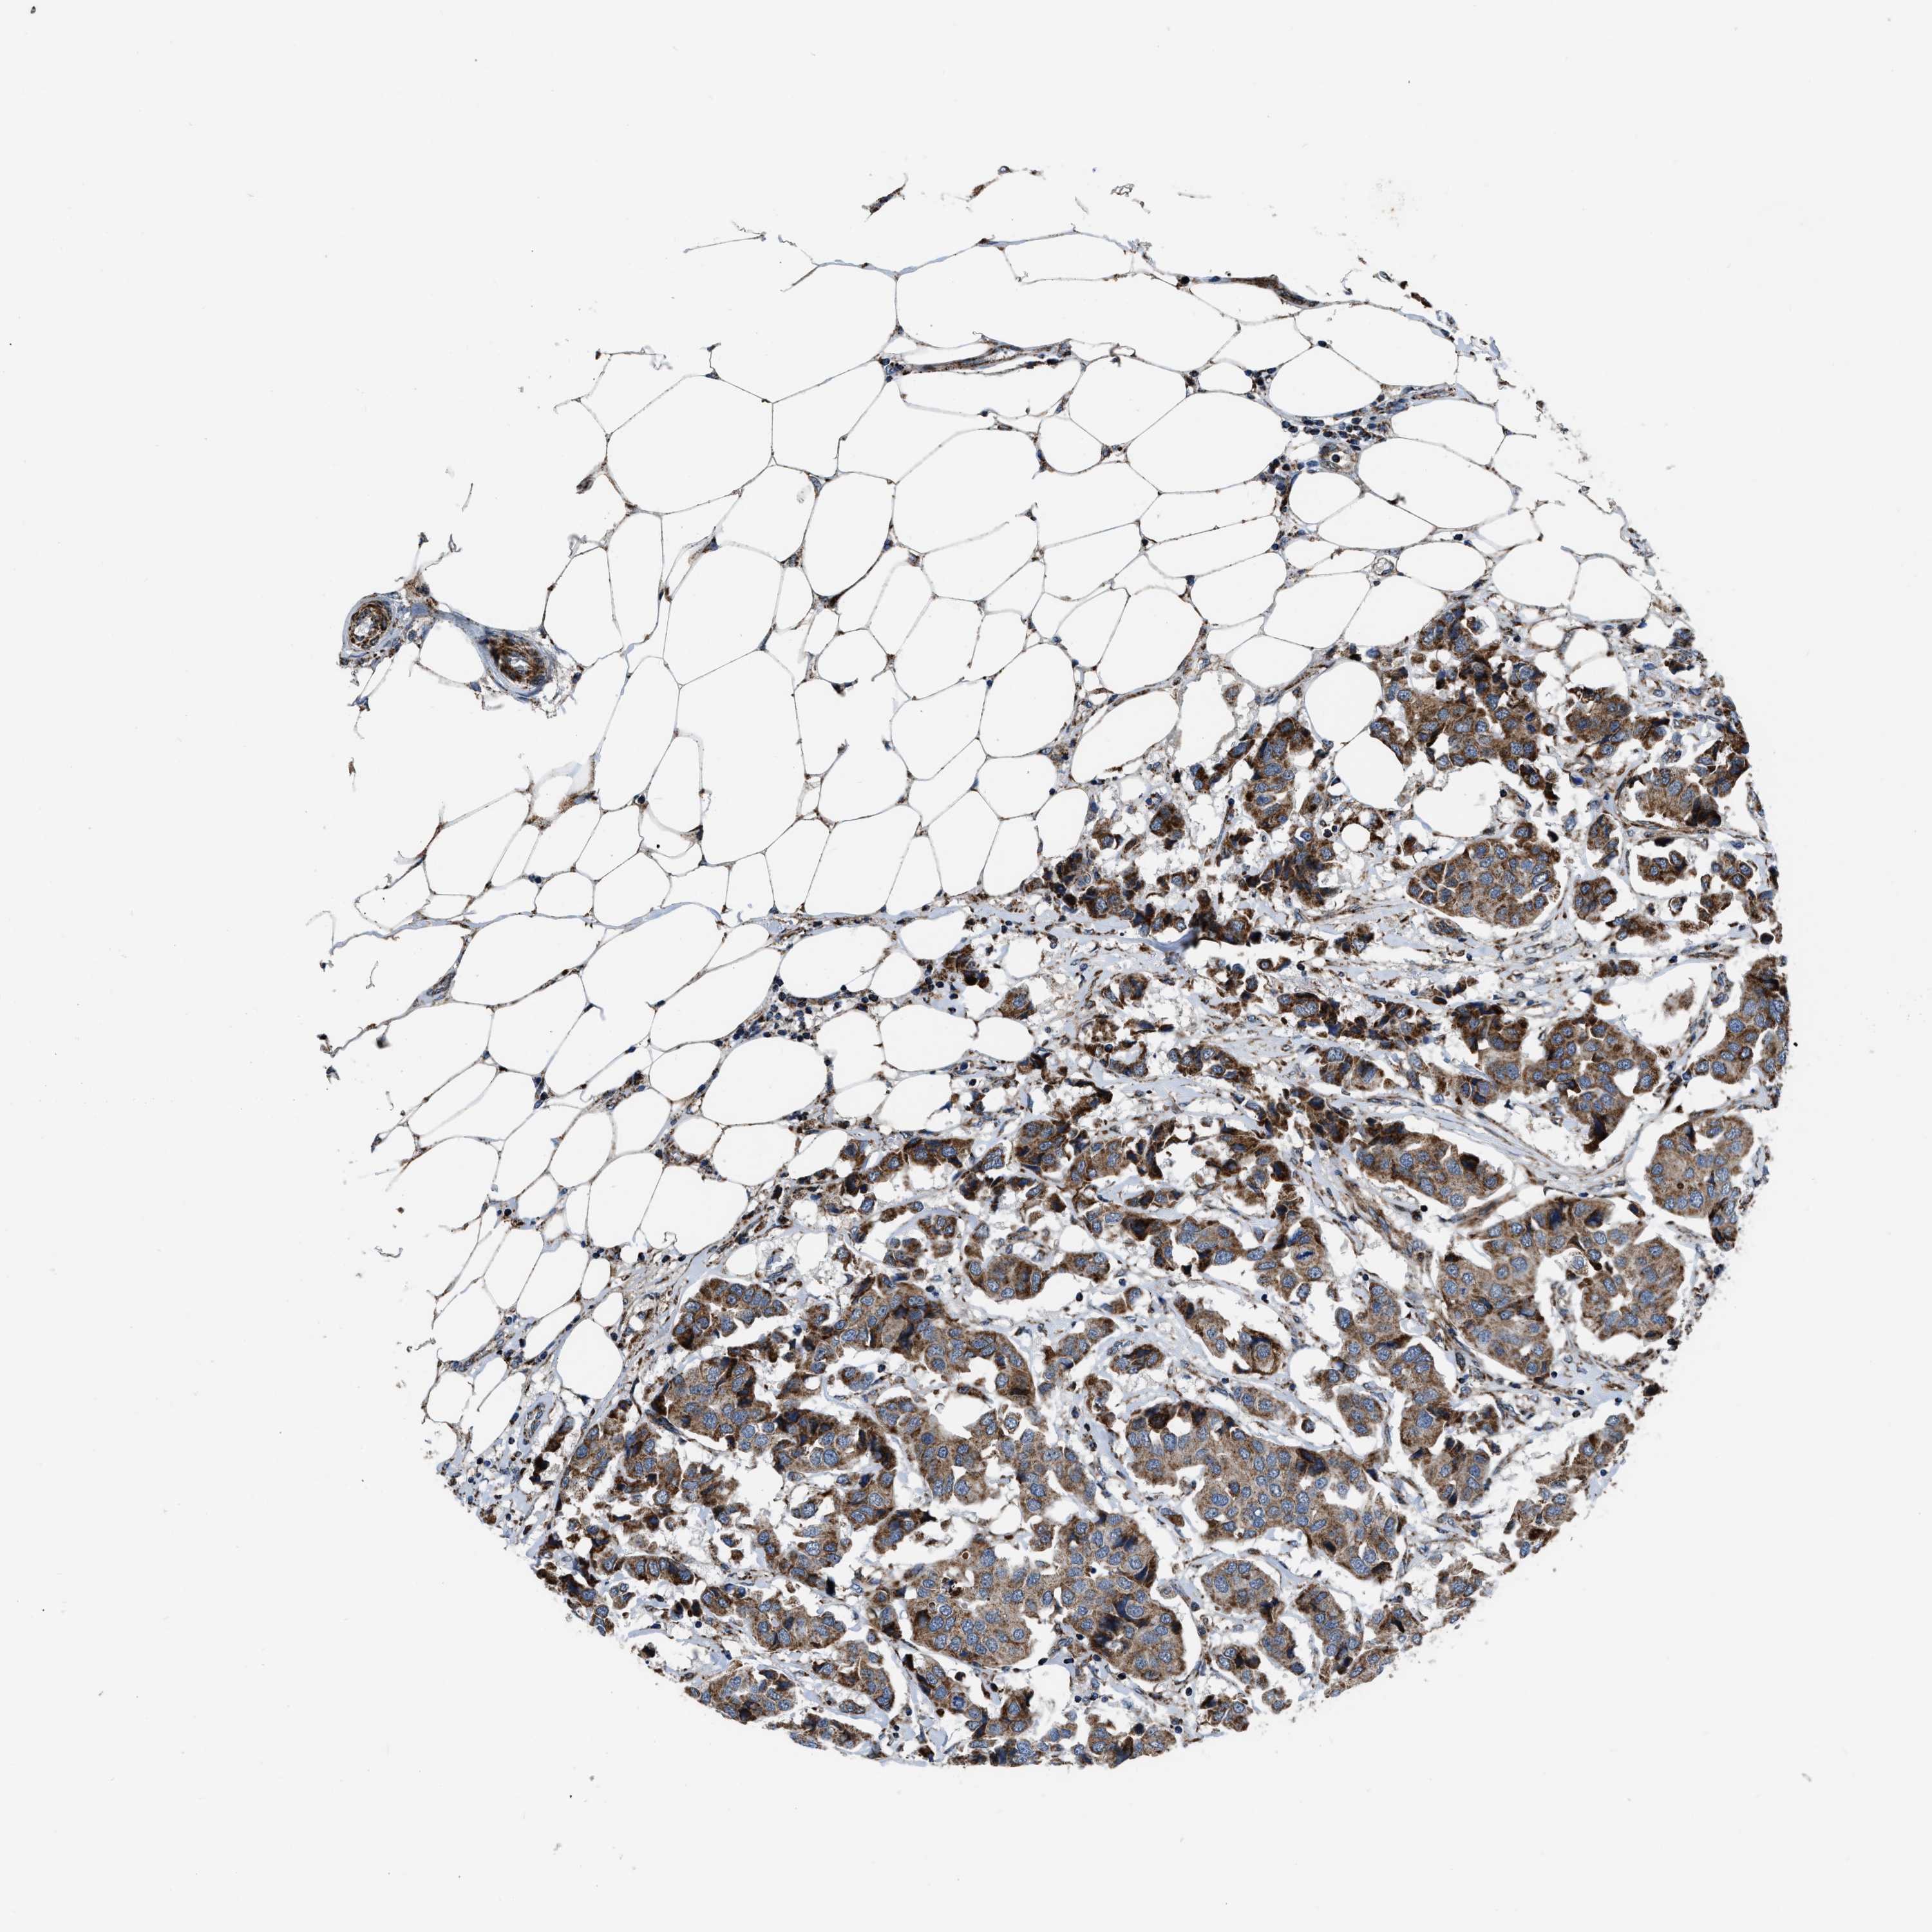

CANCER BREAST CANCER Show tissue menu

BRCA TCGA BRCA VALIDATION PROTEIN EXPRESSION